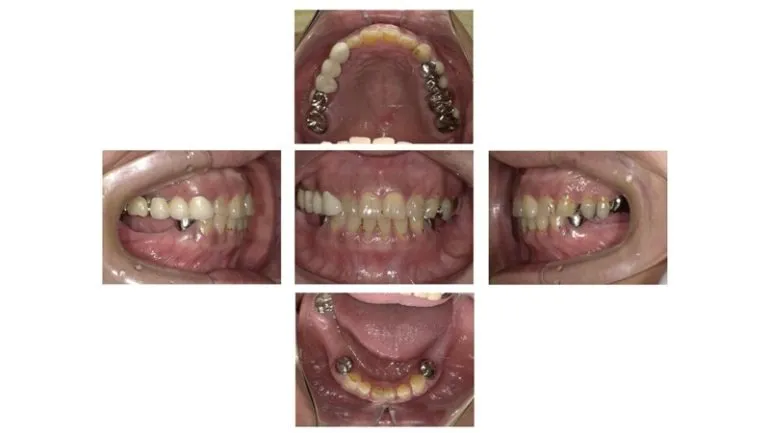

【症例4】

治療名

インプラント治療

治療説明

一番奥の歯が折れて抜歯が必要になったため、抜歯と同時に骨造成とインプラント埋入手術を行いました。その日に仮歯を装着し、3ヶ月後に最終的な型取りを行いました。痛みや腫れはほとんどなく、治療中も比較的自由に食事をしていただけました。

治療期間

4ヶ月

副作用・リスク

手術中に神経や血管を傷付ける可能性があります。痛み、腫れ、出血があります。インプラントの初期固定が取れない場合、治療期間が長引いたり、すぐに仮歯を装着できない場合があります。

料金

¥787,600(税込)